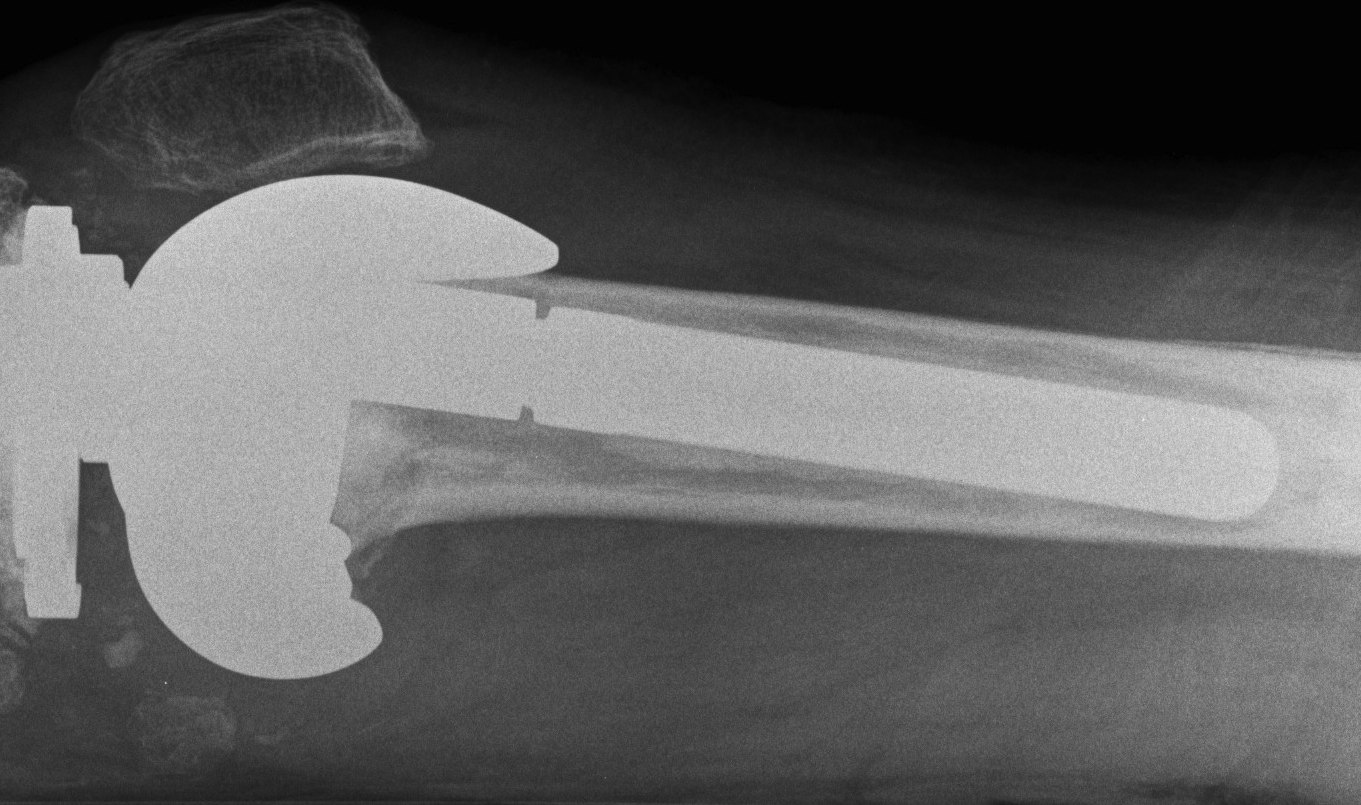

Prepare Femur

Insert trial intramedullary stem

Find IM canal

- entry point important

- if too posterior will flex femur

- if too anterior will extend femur

Ream until press fit

- insert desired length of stem

Distal femoral Cut

Distal cutting block on stem

- want to freshen surfaces minimally

- 1-2 mm off distal surface only

- consider distal femoral augments

- wait to trial extension gap to decide distal femoral augments

AP sizing

Posterior femoral condyles frequently deficient

- require augment posteriorly

- use anatomically sized femoral component

- template from other knee or use previous size from primary

- add augments posteriorly as

May need offset so femoral component sits on IM stem